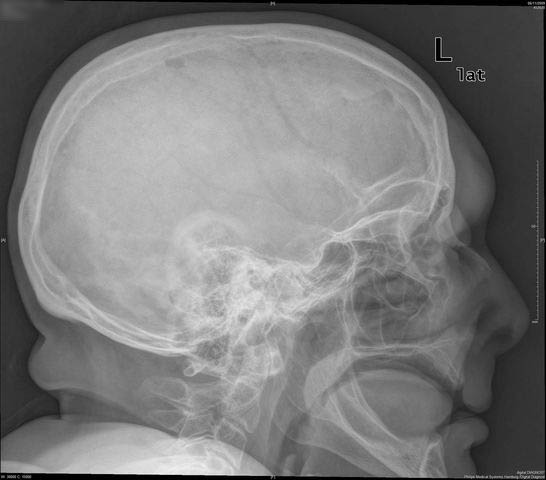

Hiperostosis craneal.